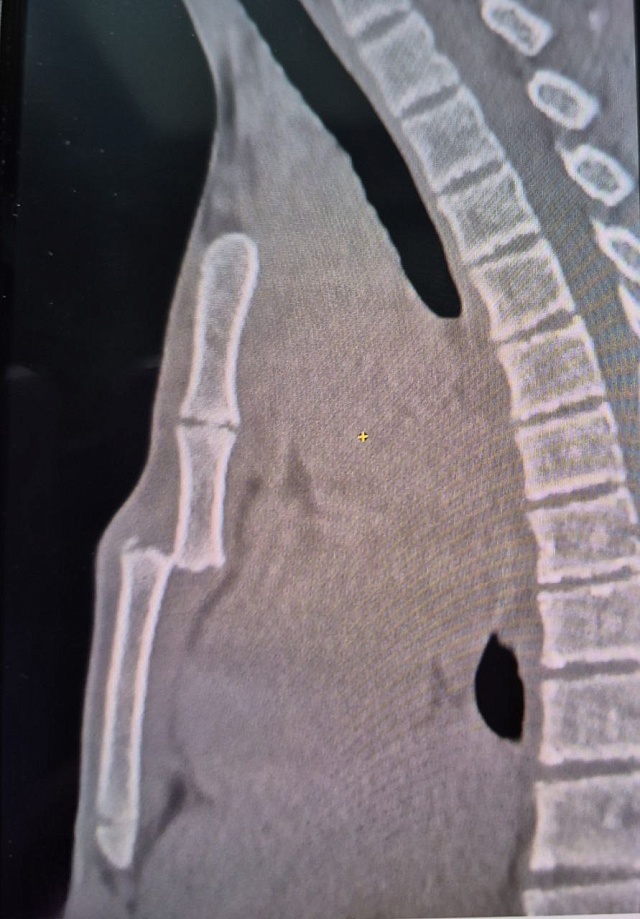

По словам заведующего детским хирургическим отделением больницы Валерия Захарова, у пациента диагностирован перелом грудины со смещением, что является довольно редким случаем. За 30 лет практики такое впервые, отметил врач.

По словам Захарова, грудина у человека становится сплошной в возрасте от 12 до 25 лет, и в данном случае перелом мог произойти в зоне роста, что объясняет травму.

"По всей видимости, наш пациент сломал грудину по зоне роста. Если бы она у него была уже сплошной, он бы её не сломал", - подытожил Валерий Захаров.